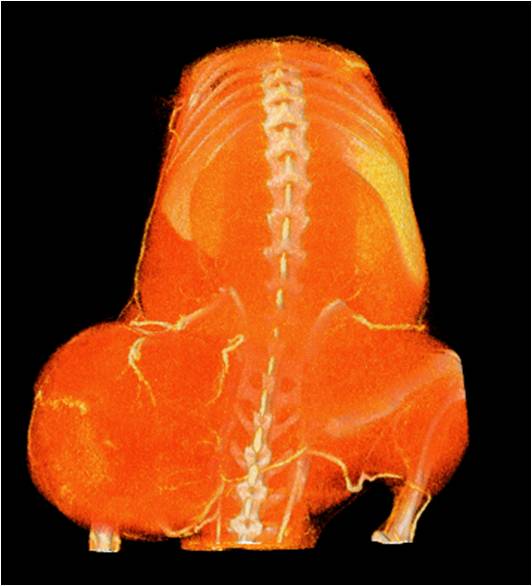

心血管

胸部和心血管的層析成像 胸部和心血管的3D圖像